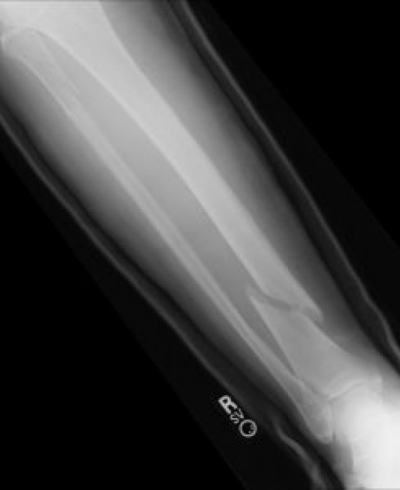

뼈의 강도가 약해져서 쉽게 골절되는 골격계 질환이다. 나이가 들면서 뼈 속의 칼슘이 밖으로 빠져나가게 되면서 노화가 주 원인이다. 여성의 경우 폐경 후 골 소실이 급속히 일어난다. 이는 여성 호르몬의 결핍 때문이다. 손목뼈, 척추, 고관절에서 골절이 자주 발생한다.

대부분 없지만 골절이 생기면 통증이 발생한다. 골절이 발생한 부위에 따라 다른 증상이 나타날 수 있다.